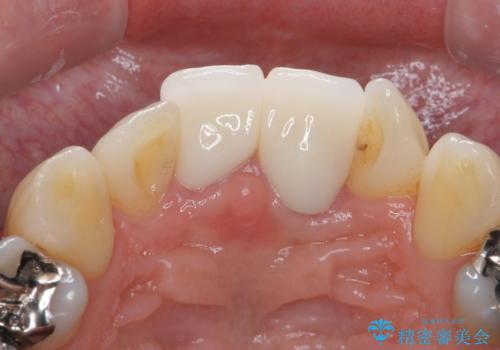

前歯をキレイにしたい ジルコニアクラウンでの治療

- 前歯の変色とガタつきがきになるとのことで来院されました。

矯正治療の希望はなかったため、セラミッククラウンで被せて治療していくことになりました。

歯をある程度削ることにはなりますが、被せ物にすることで歯の変色を隠し短期間でキレイな口元に仕上げることができました。

前歯の色・形・ガタつきともに改善することができ、大変喜んでいただけました。